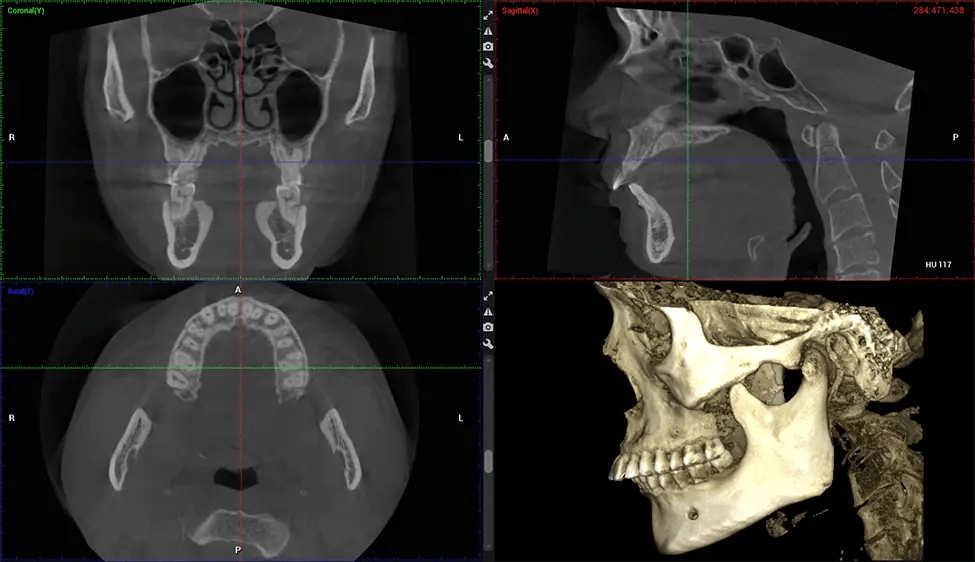

There are many benefits to using CBCT technology, especially compared to the traditional 2D X-ray format. One of the most significant advantages of CBCT scans is that they provide much more information than traditional X-rays. A scan lets your dentist see images from all angles of your jaw and mouth, including your sinuses, nasal cavity, cheekbones, and other surrounding areas. This added information helps your dentist craft a comprehensive treatment plan that addresses all aspects of your oral health.

ENT Physician Diagnosing obstructive sleep apnea (OSA) and evaluating sinus and nasal cavity anatomy. Visualizes the entire pharyngeal airway to measure volume, pinpoint constrictions, and plan corrective surgery if needed.

Planmeca Viso G7 CBCT ( Cone Beam CT Scan ) is designed to surpass the demands of industry leaders, specialists, and large institutions. It’s has a large ø25×30 cm sensor with four built-in cameras. It can capture unlimited volume sizes from a ø3×3 cm to a ø30x30cm volume capturing the skullcap through C7 on the cervical spine. The Planmeca Viso G7 offers the industry’s largest single volume scan of ø30×19 cm. It’s poised to handle advanced imaging modalities such as Planmeca ProFace® and Planmeca 4D™ Jaw Motion technology. The occipital head support allows an unimpeded view of facial tissue.